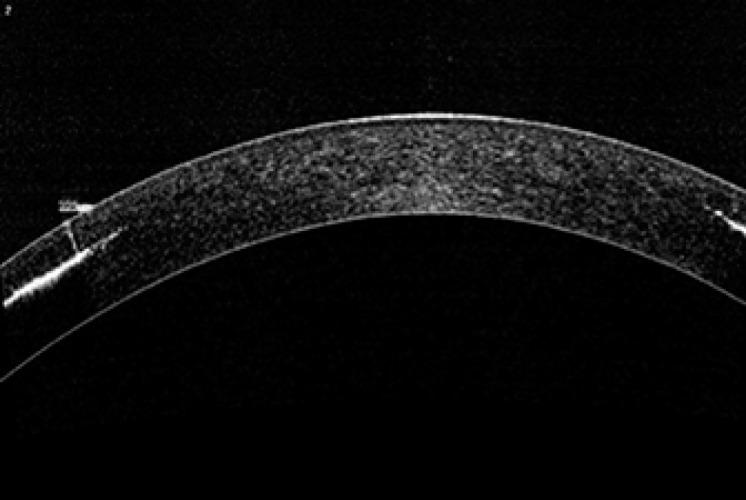

A 21-year-old female patient in good general and ophthalmological health with the wish to change the colour of her eyes was treated with a femtosecond-assisted annular keratopigmentation technique. Pigment was inserted in a channel in the cornea (external diameter 9.3 mm; internal diameter 5.5 mm) created with a femtosecond laser at a depth of 225 μm. Eight months post-operatively, there were no signs of leakage, diffusion, inflammation or any other detrimental effects on the cornea both objectively and subjectively.

一名21岁女性患者,全身及眼部健康状况良好,希望改变眼睛颜色,接受了飞秒辅助环形角膜色素沉着技术治疗。使用飞秒激光在角膜上制作一个通道(外径9.3毫米;内径5.5毫米),深度为225微米,并在通道内植入色素。术后八个月,无论客观还是主观上,均未出现渗漏、扩散、炎症或对角膜的任何其他有害影响迹象。